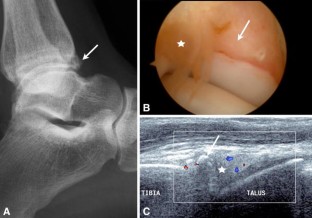

Fig. 1